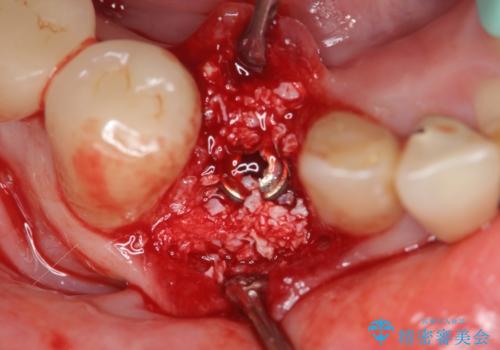

X線写真および歯周組織検査より、歯の破折 周囲骨の高度な吸収が認められました。

抜歯後、インプラントによる審美・機能改善を希望されたのでインプラント埋入に先立ち吸収した骨の再生を計画します。

歯を失う原因が虫歯や根尖病変などはなく、歯周病や歯の破折等周囲の骨を吸収する原因の場合はインプラント治療を行うに先立ち骨の造成が必要なことがあります。